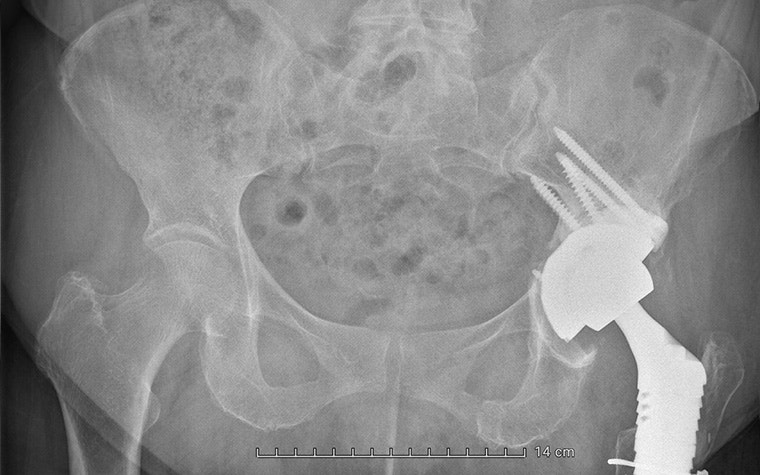

A few years ago, she suffered a periprosthetic fracture of the femur caused by polyethylene wear. Dr. Van Overschelde performed revision surgery with a REEF prosthesis on the femoral side and an acetabular revision with a revision cup and augment.

Then, six months ago, the patient began experiencing ongoing groin pain and difficulty walking after a fall. A CT scan revealed another periprosthetic acetabular fracture with a complete dissociation of the pelvis. The fracture was severe enough that natural healing was, unfortunately, not occurring.

Beyond these complications, the patient also had severe osteoporosis and a history of pseudo-tumor development, resulting in significant bone destruction. It was no straightforward case for Dr. Van Overschelde, and he had to navigate many complexities to restore function and minimize the risk of future medical interventions.

The aMace implant helps surgeons break the revision cycle. It is designed for minimal risk of dislocation, is based on unique 3D pelvis analyses to quantify bone loss and available bone stock, and makes long-term fixation possible with crossed screw trajectories and a defect-filling porous augment.